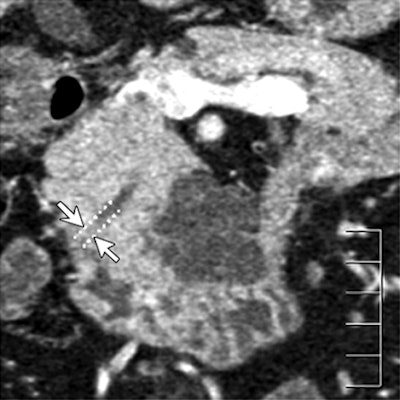

| Dilatation of main pancreatic duct (MPD) in intraductal papillary mucinous neoplasms of the pancreas (IPMN). Oblique coronal reformatted images were generated from pancreatic phase scanning, with 5-cm scale at lower right on each image. Above, adenoma; below, noninvasive carcinoma; bottom, invasive carcinoma. As the maximum diameter of the MPD (arrows indicate distance between dotted lines) increased by 3.8 mm (top), 21.4 mm (below), and 40.9 mm (bottom), the likelihood of malignancy of IPMN increased. Arrowhead on image below indicates protrusion of dilated MPD, showing water attenuation into the ampulla of Vater. Many mural nodules are seen in dilated MPD in invasive carcinoma on bottom image. |

The following findings showed significant differences among the three groups: maximum diameter of the main pancreatic duct (MPD), size (length of major axis) of the largest mural nodule in the MPD or in any associated cystic lesion, abnormal attenuating area in the surrounding parenchyma, calcification in the lesion, protrusion of the MPD into the ampulla of Vater, and bile duct dilatation, the authors reported.

"Of seven findings that were significant predictors of invasion in the univariate analysis, the following two findings remained significant in the multivariate analysis: presence of a mural nodule in the MPD of 6.3 mm or larger, and presence of an abnormal attenuating area in the surrounding parenchyma," the authors wrote.

When tumors meeting one or both of these criteria were identified as invasive, CT's sensitivity, specificity, and accuracy for detecting parenchymal invasion were 90%, 88%, and 89%, respectively.